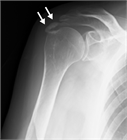

1. 急性の石灰沈着性滑液包炎は、腱板内に沈着した石灰が肩峰下滑液包へ流出して発生する結晶性滑液包炎である。突然発症する例が多い。

1. 腱板内に沈着した石灰が大きくなり、慢性化してインピンジメント症状や関節拘縮を引き起こすこともある。

1. 無症候性の石灰沈着症の発生率は人口の2.7~20%で、30~50歳に好発する。有症状の沈着症は50歳前後であり、女性(男女比は3:2)と棘上筋腱に多い。